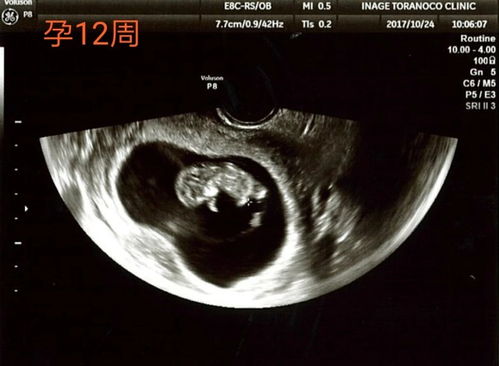

在孕期,B超检查是监测胎儿发育状况的重要手段之一。尤其是到了孕23周,系统B超检查不仅能够帮助医生全面评估胎儿的生长发育,还能排查一些潜在的异常情况。本文将为您详细解读孕23周系统B超数据,帮助您了解这一重要时刻的胎儿发育状况。

系统B超检查,也称为大排畸B超,是孕期中非常重要的一项检查。它主要针对胎儿的各个器官和系统进行全面的检查,以评估胎儿的生长发育状况,排查潜在的畸形和异常。